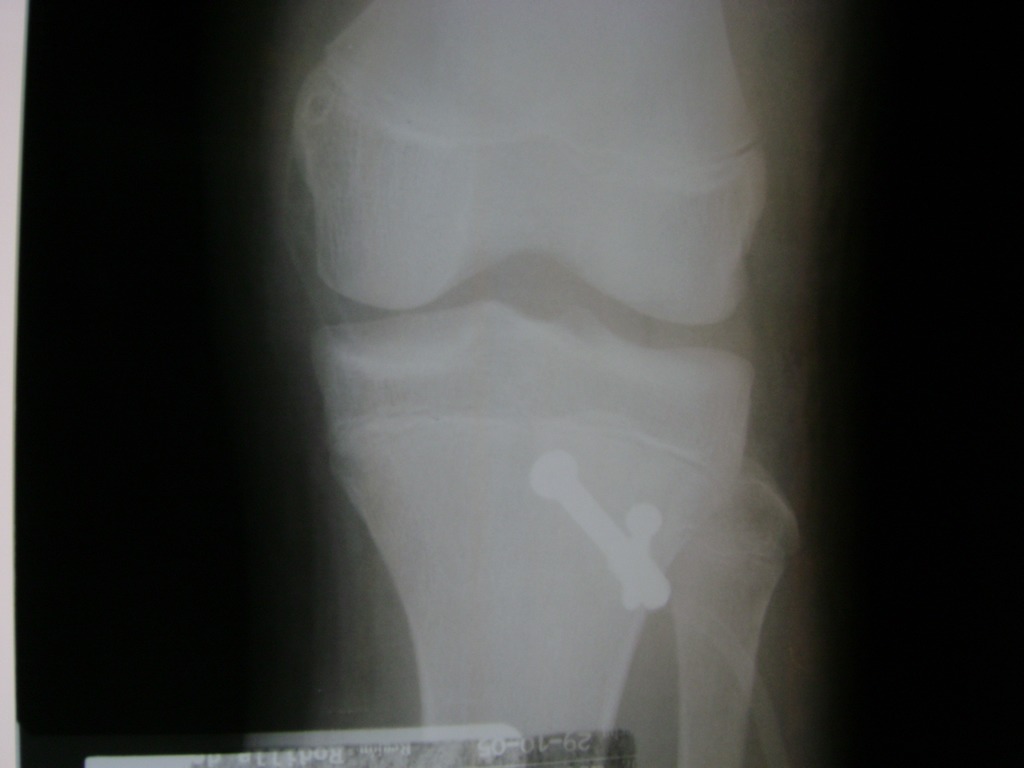

Húmero - Rodilla